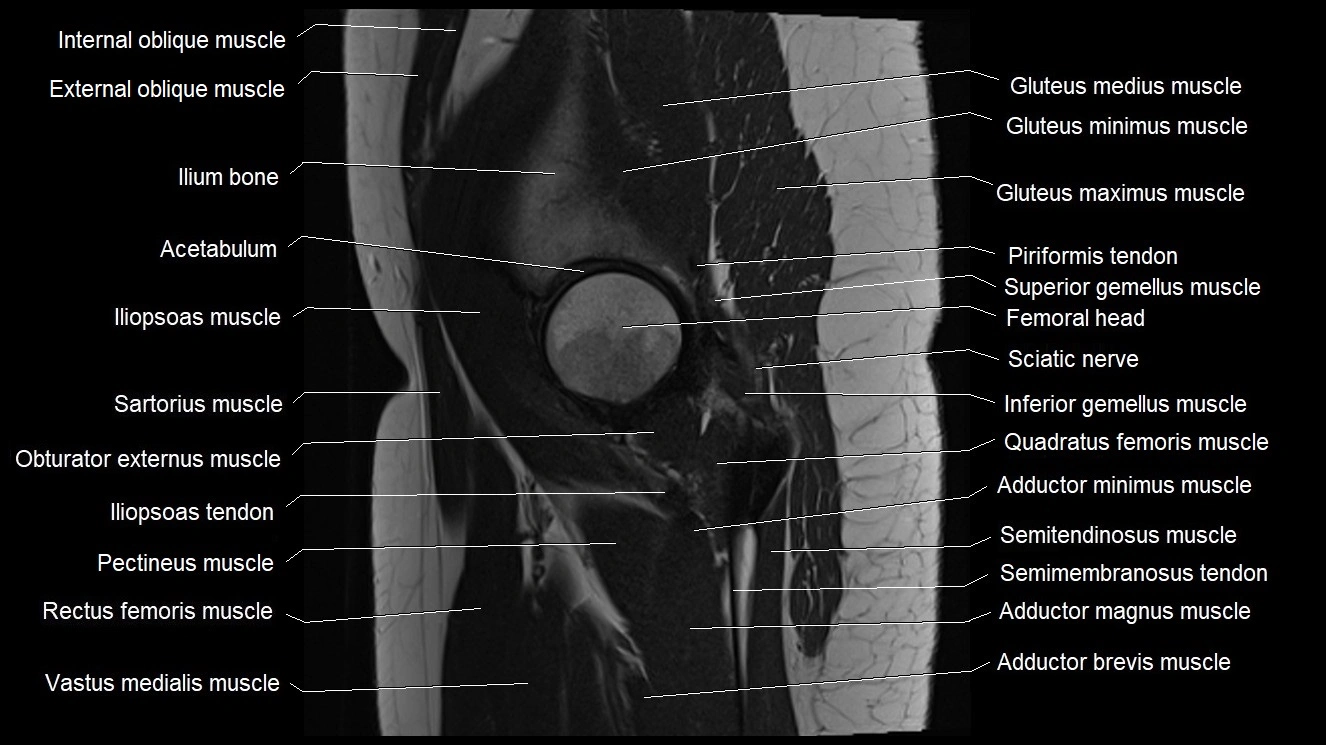

- Acetabulum

- Adductor brevis muscle

- Adductor magnus muscle

- Adductor minimus muscle

- Head of femur

- Iliopsoas muscle

- Iliopsoas tendon

- Ilium bone

- Inferior gemellus muscle

- Obturator externus muscle

- Pectineus muscle

- Quadratus femoris muscle

- Rectus femoris muscle

- Sartorius muscle

- Superior gemellus muscle

- Vastus intermedius muscle

- Vastus lateralis muscle

- Vastus medialis muscle